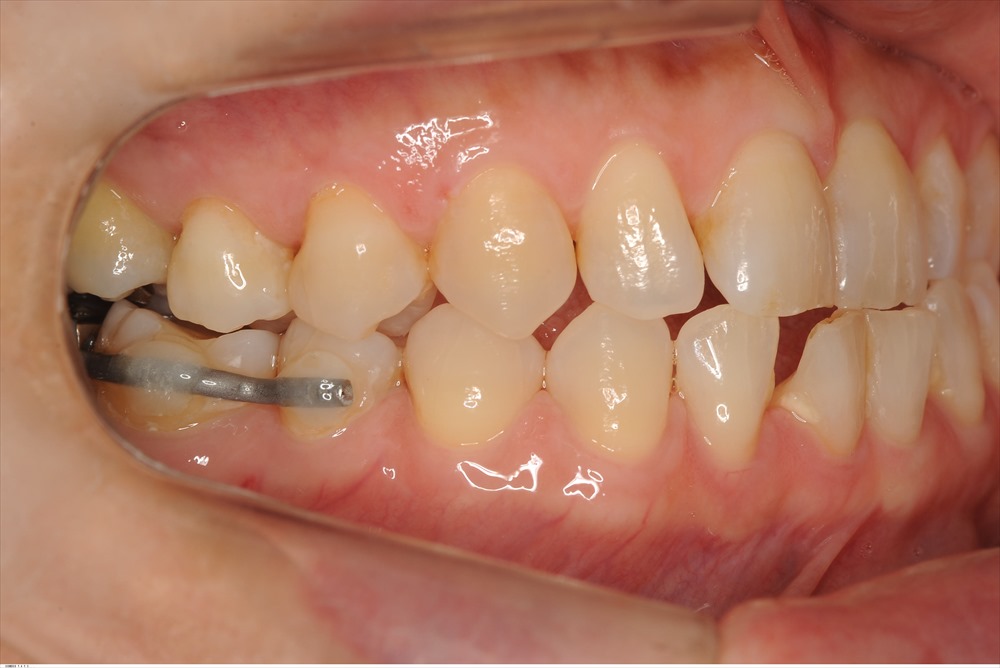

約4ヶ月

歯肉は安定し、骨様組織が出来ている様に見えます。この症例は一切、再生材料などを使用していません。